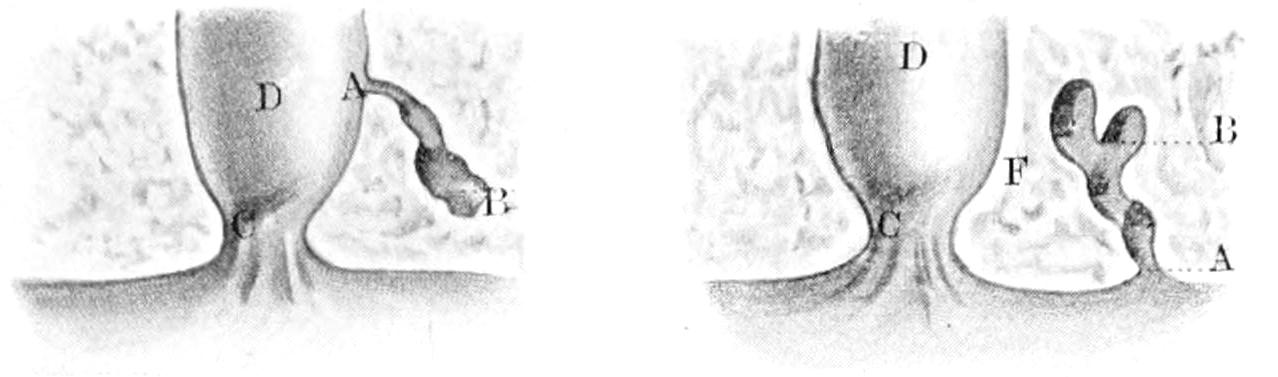

THE BLADDER AND PROSTATE 977